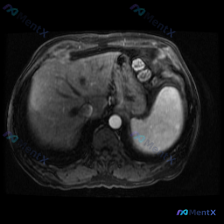

- 序列:腹部MRI轴位T1加权像

- 覆盖范围:上腹部(肝左/右叶部分、脾脏、胰腺体尾、胃泡、腹主动脉)

- 图像质量:信噪比良好,无明显运动伪影

- 肝实质整体信号尚均匀

- 肝左叶见一类圆形低信号灶,边界尚清,信号较周围肝实质稍低